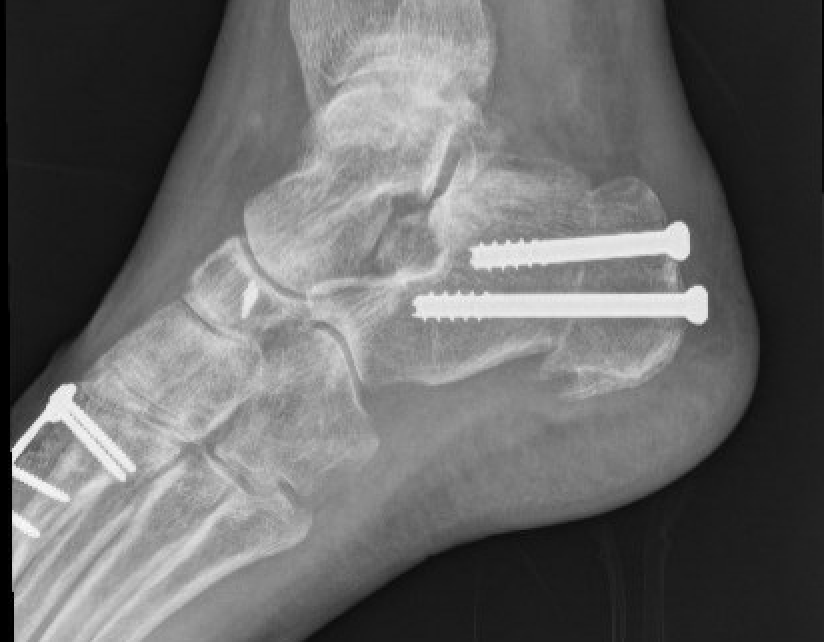

Dwyer lateral closing wedge calcaneal osteotomy

Indication

Fixed hindfoot varus

Technique

Lateral approach

- posterior and inferior to peroneal tendons

- resect lateral wedge of bone

- reduce calcaneal ostoeotmy and fix with screws

Lateral displacement calcaneal osteotomy

- curve just behind peroneals

- homann in front of tendoachilles

- homann under calcaneum

Oblique osteotomy behind posterior facet

- 45o

- open with lamina spreader

- split periosteum medially with osteotome

- avoid damage to medial structures

- transfer laterally 1 cm

- screw fixation